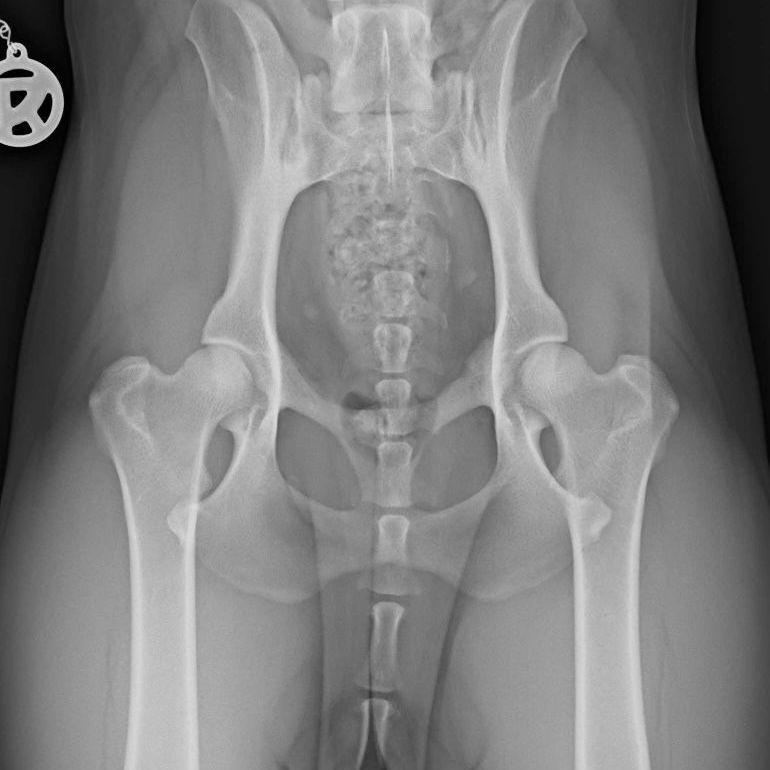

Bevor eine manuelle Therapie beim Hund durchgeführt wird, erfolgt in meiner Praxis zunächst eine genaue Untersuchung, welche ggf. auch mit einer Diagnose beim Tierarzt (z.B. bildgebender Diagnostik) kombiniert wird, um die geeignete Behandlungsmethode festzustellen. In vielen Fällen kombiniere ich die manuelle Therapie auch mit anderen Therapieformen wie Lasertherapie oder der Behandlung mit dem Novafon, um optimale Ergebnisse zu erzielen.